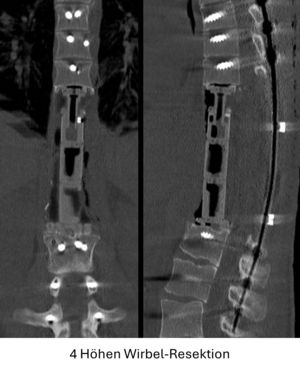

Seit 2017 führen wir unsere Stabilisierungs- und Versteifungsoperationen mit einem intraoperativen CT (s.o. AIRO©, Fa. Brainlab) durch. Diese intraoperative Computertomographie liefert direkt im Operationssaal während des Eingriffs hochauflösende Bilder von der Wirbelsäule. Zusammen mit einer Navigationssoftware wird ein dreidimensionaler Plan der entsprechenden Körperregion erzeugt. Mit Hilfe der Bildgebung können wir die notwendigen OP-Schritte plangerecht umsetzen und z.B. Implantate mit sehr hoher Präzision einsetzen. Gerade bei komplizierten Eingriffen an der Wirbelsäule hilft die neue OP-Technik, Patienten sicher und schonend zu therapieren. Die intraoperative Bildgebung, direkt im OP, erlaubt komplexe Operationen genauer und sicherer durchzuführen und dem Operateur noch während der Operation das Ergebnis zu überprüfen und bei Bedarf zu optimieren. Belastende Folgeoperationen sind so deutlich seltener und die Behandlungsqualität und Sicherheit für Patienten dadurch erheblich verbessert.